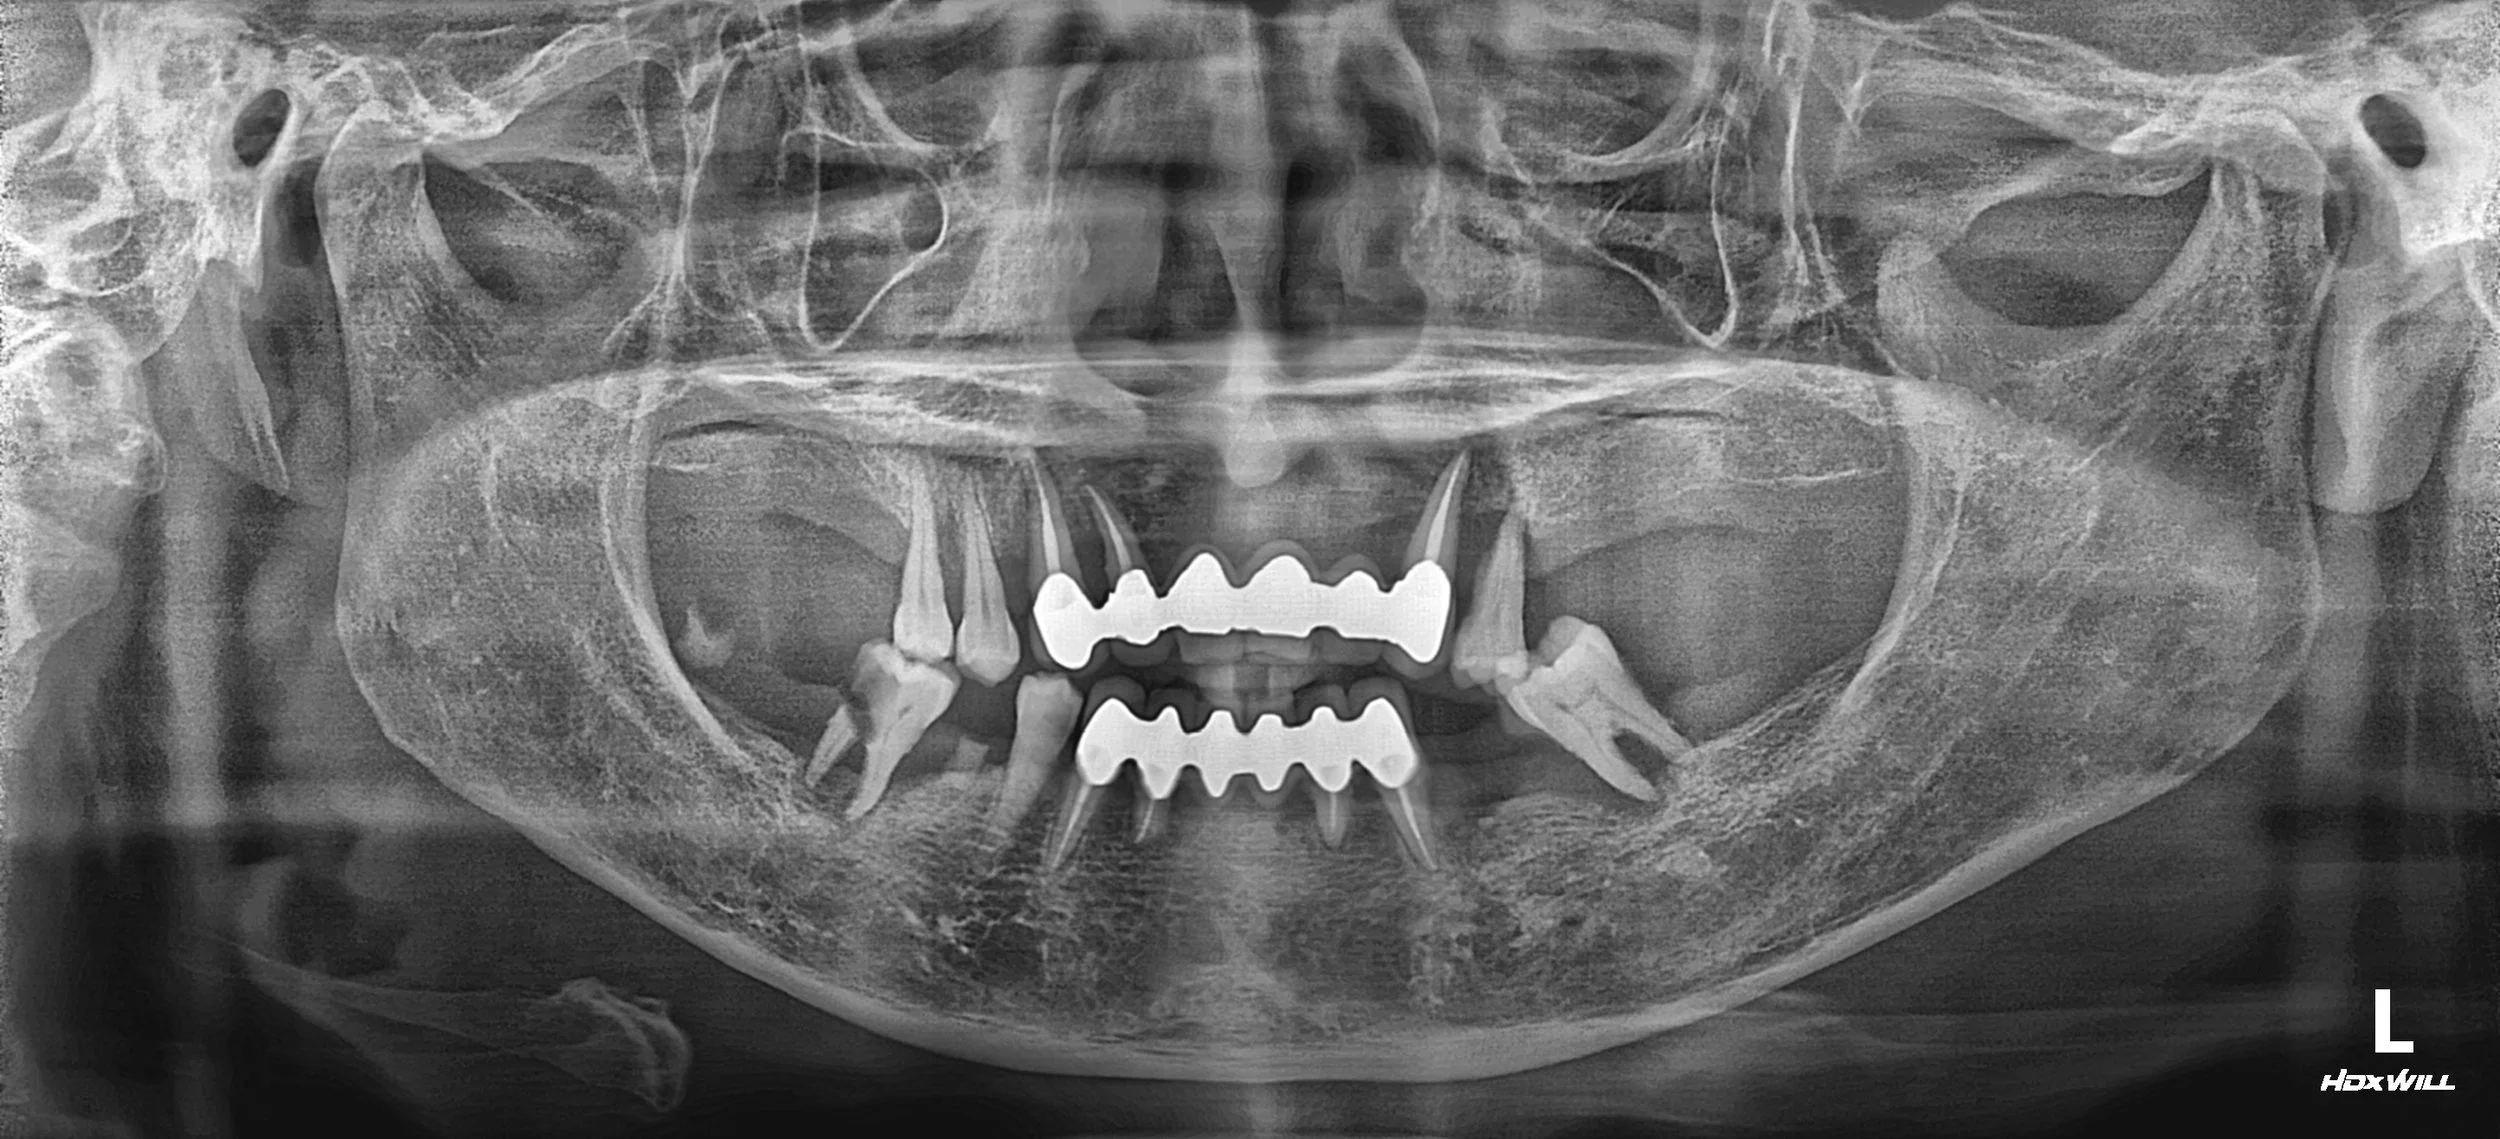

OPG - BEFORE

A female patient in her 60s presented with a severely compromised dentition and a completely collapsed occlusal relationship. Long-standing periodontal disease had led to:

• Generalized Periodontal Breakdown: Extensive mobility and loss of supporting structures across both arches.

• Poor Alveolar Bone Quality: Significant resorption of the alveolar ridge, complicating the foundation for implant placement.